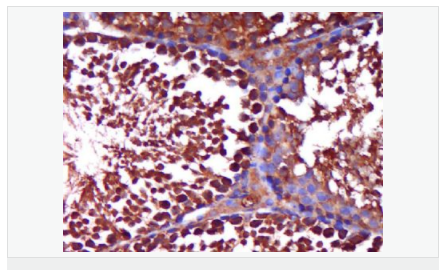

| 產(chǎn)品應(yīng)用 | WB=1:500-2000 ELISA=1:5000-10000 IHC-P=1:100-500 IHC-F=1:100-500 Flow-Cyt=1ug/Test IF=1:100-500 (石蠟切片需做抗原修復(fù)) not yet tested in other applications. optimal dilutions/concentrations should be determined by the end user. |

| 產(chǎn)品介紹 | The androgen receptor gene is more than 90 kb long and codes for a protein that has 3 major functional domains: the N-terminal domain, DNA-binding domain, and androgen-binding domain. The protein functions as a steroid-hormone activated transcription factor. Upon binding the hormone ligand, the receptor dissociates from accessory proteins, translocates into the nucleus, dimerizes, and then stimulates transcription of androgen responsive genes. This gene contains 2 polymorphic trinucleotide repeat segments that encode polyglutamine and polyglycine tracts in the N-terminal transactivation domain of its protein. Expansion of the polyglutamine tract causes spinal bulbar muscular atrophy (Kennedy disease). Mutations in this gene are also associated with complete androgen insensitivity (CAIS). Two alternatively spliced variants encoding distinct isoforms have been described. [provided by RefSeq, Jul 2008] Function: Steroid hormone receptors are ligand-activated transcription factors that regulate eukaryotic gene expression and affect cellular proliferation and differentiation in target tissues. Transcription factor activity is modulated by bound coactivator and corepressor proteins. Transcription activation is down-regulated by NR0B2. Activated, but not phosphorylated, by HIPK3 and ZIPK/DAPK3. [ENZYME REGULATION] AIM-100 (4-amino-5,6-biaryl-furo[2,3-d]pyrimidine) suppresses TNK2-mediated phosphorylation at Tyr-267. Inhibits the binding of the Tyr-267 phosphorylated form to androgen-responsive enhancers (AREs) and its transcriptional activity. Subunit: Binds DNA as a homodimer. Part of a ternary complex containing AR, EFCAB6/DJBP and PARK7. Interacts with HIPK3 and NR0B2 in the presence of androgen. The ligand binding domain interacts with KAT7/HBO1 in the presence of dihydrotestosterone. Interacts with EFCAB6/DJBP, PELP1, PQBP1, RANBP9, RBAK, SPDEF, SRA1, TGFB1I1, ZNF318 and RREB1. Interacts with ZMIZ1/ZIMP10 and ZMIZ2/ZMIP7 which both enhance its transactivation activity. Interacts with SLC30A9 and RAD54L2/ARIP4. Interacts via the ligand-binding domain with LXXLL and FXXLF motifs from NCOA1, NCOA2, NCOA3, NCOA4 and MAGEA11. The AR N-terminal poly-Gln region binds Ran resulting in enhancement of AR-mediated transactivation. Ran-binding decreases as the poly-Gln length increases. Interacts with HIP1 (via coiled coil domain). Interacts (via ligand-binding domain) with TRIM68. Interacts with TNK2. Interacts with USP26. Interacts with RNF6. Interacts (regulated by RNF6 probably through polyubiquitination) with RNF14; regulates AR transcriptional activity. Interacts with PRMT2 and TRIM24. Interacts with GNB2L1/RACK1. Interacts with RANBP10; this interaction enhances dihydrotestosterone-induced AR transcriptional activity. Interacts with PRPF6 in a hormone-independent way; this interaction enhances dihydrotestosterone-induced AR transcriptional activity. Interacts with STK4/MST1. Interacts with ZIPK/DAPK3. Interacts with LPXN. Interacts with MAK. Part of a complex containing AR, MAK and NCOA3. Subcellular Location: Nucleus. Cytoplasm. Note=Predominantly cytoplasmic in unligated form but translocates to the nucleus upon ligand-binding. Can also translocate to the nucleus in unligated form in the presence of GNB2L1. Tissue Specificity: Isoform 2 is mainly expressed in heart and skeletal muscle. Post-translational modifications: Sumoylated on Lys-386 (major) and Lys-520. Ubiquitinated. Deubiquitinated by USP26. 'Lys-6' and 'Lys-27'-linked polyubiquitination by RNF6 modulates AR transcriptional activity and specificity. Phosphorylated in prostate cancer cells in response to several growth factors including EGF. Phosphorylation is induced by c-Src kinase (CSK). Tyr-534 is one of the major phosphorylation sites and an increase in phosphorylation and Src kinase activity is associated with prostate cancer progression. Phosphorylation by TNK2 enhances the DNA-binding and transcriptional activity and may be responsible for androgen-independent progression of prostate cancer. Phosphorylation at Ser-81 by CDK9 regulates AR promoter selectivity and cell growth. Phosphorylation by PAK6 leads to AR-mediated transcription inhibition. Palmitoylated by ZDHHC7 and ZDHHC21. Palmitoylation is required for plasma membrane targeting and for rapid intracellular signaling via ERK and AKT kinases and cAMP generation. DISEASE: Defects in AR are the cause of androgen insensitivity syndrome (AIS) [MIM:300068]; previously known as testicular feminization syndrome (TFM). AIS is an X-linked recessive form of pseudohermaphroditism due end-organ resistance to androgen. Affected males have female external genitalia, female breast development, blind vagina, absent uterus and female adnexa, and abdominal or inguinal testes, despite a normal 46,XY karyotype. Defects in AR are the cause of spinal and bulbar muscular atrophy X-linked type 1 (SMAX1) [MIM:313200]; also known as Kennedy disease. SMAX1 is an X-linked recessive form of spinal muscular atrophy. Spinal muscular atrophy refers to a group of neuromuscular disorders characterized by degeneration of the anterior horn cells of the spinal cord, leading to symmetrical muscle weakness and atrophy. SMAX1 occurs only in men. Age at onset is usually in the third to fifth decade of life, but earlier involvement has been reported. It is characterized by slowly progressive limb and bulbar muscle weakness with fasciculations, muscle atrophy, and gynecomastia. The disorder is clinically similar to classic forms of autosomal spinal muscular atrophy. Note=Caused by trinucleotide CAG repeat expansion. In SMAX1 patients the number of Gln ranges from 38 to 62. Longer expansions result in earlier onset and more severe clinical manifestations of the disease. Note=Defects in AR may play a role in metastatic prostate cancer. The mutated receptor stimulates prostate growth and metastases development despite of androgen ablation. This treatment can reduce primary and metastatic lesions probably by inducing apoptosis of tumor cells when they express the wild-type receptor. Defects in AR are the cause of androgen insensitivity syndrome partial (PAIS) [MIM:312300]; also known as Reifenstein syndrome. PAIS is characterized by hypospadias, hypogonadism, gynecomastia, genital ambiguity, normal XY karyotype, and a pedigree pattern consistent with X-linked recessive inheritance. Some patients present azoospermia or severe oligospermia without other clinical manifestations. Similarity: Belongs to the nuclear hormone receptor family. NR3 subfamily. Contains 1 nuclear receptor DNA-binding domain. SWISS: P10275 Gene ID: 367 Database links: Entrez Gene: 367 Human Entrez Gene: 11835 Mouse Omim: 313700 Human SwissProt: P10275 Human SwissProt: P19091 Mouse Unigene: 496240 Human Unigene: 39005 Mouse Unigene: 394224 Mouse Unigene: 439657 Mouse Unigene: 9813 Rat Important Note: This product as supplied is intended for research use only, not for use in human, therapeutic or diagnostic applications. AR是一個(gè)由917個(gè)氨基酸組成的蛋白質(zhì),位于雄激素靶組織細(xì)胞中或細(xì)胞表面上的特異分子部位或結(jié)構(gòu)。 AR在前列腺癌中起著重要的作用,研究表明AR的表達(dá)與組織分型形成一定的相關(guān)性 ,AR在高分化的腫瘤中表達(dá)較多,而在低分化的腫瘤中表達(dá)較少。用于前列腺癌的檢測,指導(dǎo)臨床治療,目前可用于乳腺癌、食道癌等各項(xiàng)腫瘤的研究。 |